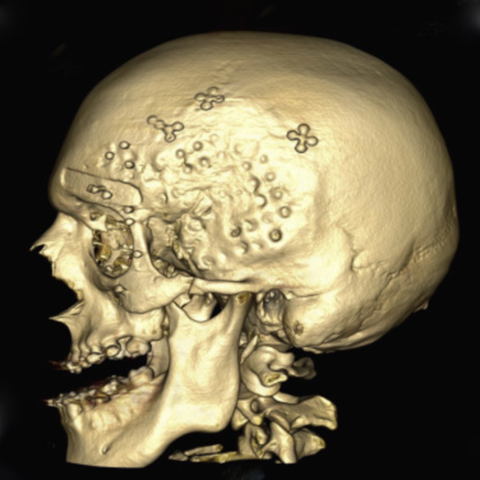

• Imágenes en 3D

Imágenes en 3D

Aparecen los equipos helicoidales con giros continuos y adquisiciones muy rápidas, efectúan imágenes al rededor de 30 por segundo Se obtienen imágenes en 3D logrando ver imágenes instantáneas de diferentes planos como axial, coronal y oblicuos